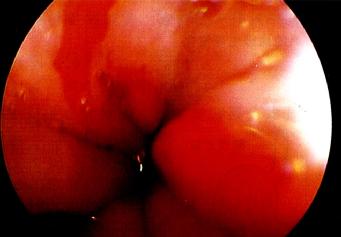

3、Barrett食管[编辑 | 编辑源代码]

【病因】

Barrett食管是慢性GERD的一种并发症。为更好地抵抗反流物的损伤,食管远端的正常鳞状上皮化生的柱状上皮所取代(图3.17)。

Barrett食管

图3.17Barrett食管。

Barrett粘膜的发生有二个重要成因:

1 食管鳞状上皮受损

2 上皮修复时食管内环境异常。

这些又可能与下列有关:

. 慢性反流性食管炎

. 十二指肠胃食管反流

. 酸清除能力减弱与以上任一因素共同存在。

诊断Barrett食管很重要,因为它与食管腺癌的发生有关。

Barrett食管的组织学类型尤为重要:只有肠型化生(以出现杯状细胞为标志)会发展为癌。

Barrett食管的内镜下所见

图3.18Barrett食管的内镜下所见。

【诊断措施】

内镜(图3.18)及活检:

确诊Barrett食管并鉴别其组织学类型、确定不典型增生及腺癌必须经内镜及活检。